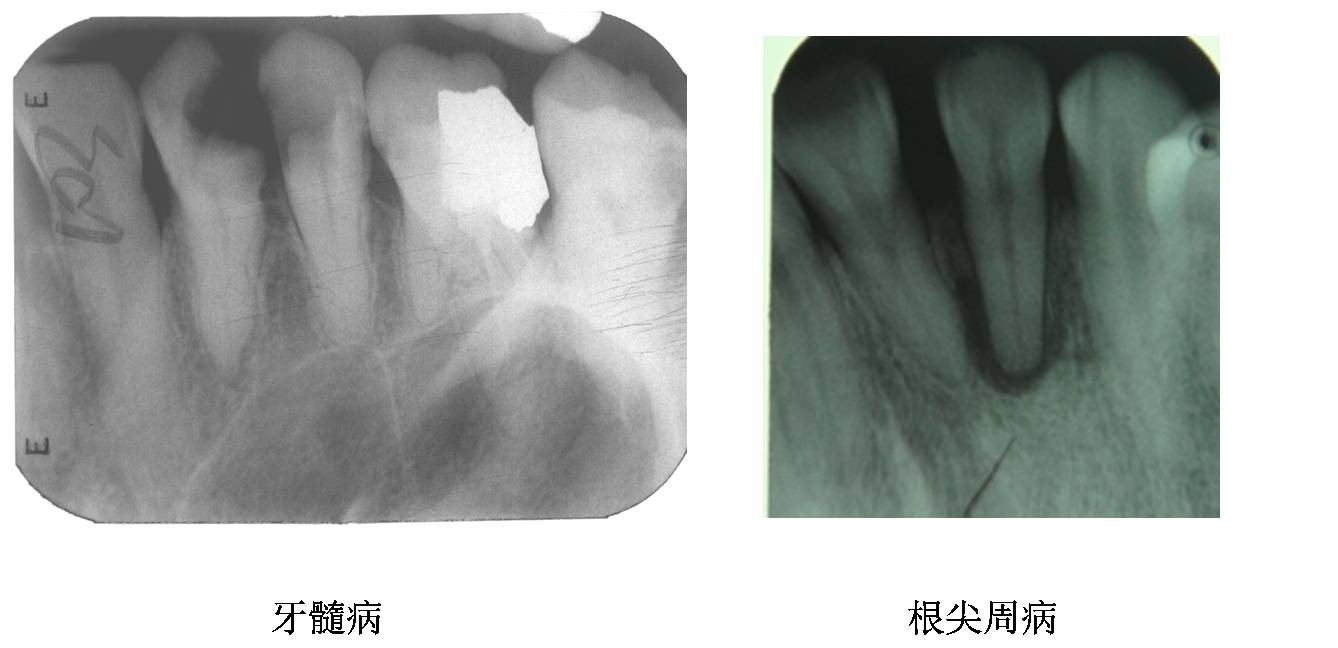

当牙髓和根尖周出现炎症时,就会导致出现牙疼的感觉,根管治疗是治疗牙髓病和根尖周病最有效的方法。